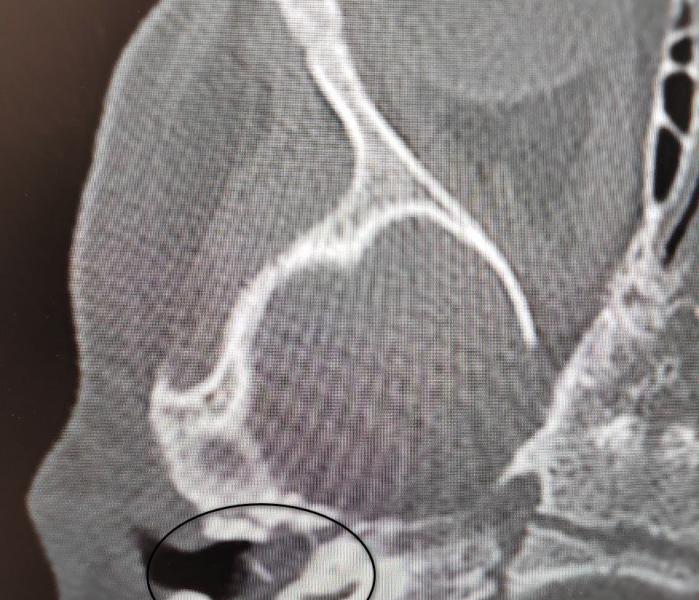

Специалисты оториноларингологического отделения Воронежской областной детской клинической больницы №1 успешно прооперировали двухлетнюю пациентку с диагностированной врожденной холестеатомой барабанной полости. Данное кистозное образование в среднем ухе редко выявляют в столь раннем возрасте – обычно заболевание обнаруживают у детей 5-8 лет.

Поводом для обращения стало ухудшение состояния после перенесенной ОРВИ: у ребенка появились боли в ухе, а консервативная терапия не принесла результатов. Ситуация осложнилась развитием пареза лицевого нерва, проявлявшегося слабостью мимических мышц. После подтверждения диагноза врачи приняли решение о проведении срочного хирургического вмешательства.

Операцию выполнил заведующий отделением Антон Мащенко, проведя аттико-антротомию с тимпанопластикой. С использованием операционного микроскопа хирург удалил холестеатому, выполнил декомпрессию лицевого нерва и восстановил механизм звукопроведения. Благодаря своевременному вмешательству медикам удалось полностью сохранить слух ребенка и восстановить функцию нерва. Девочка была выписана домой на пятые сутки после операции без каких-либо осложнений.